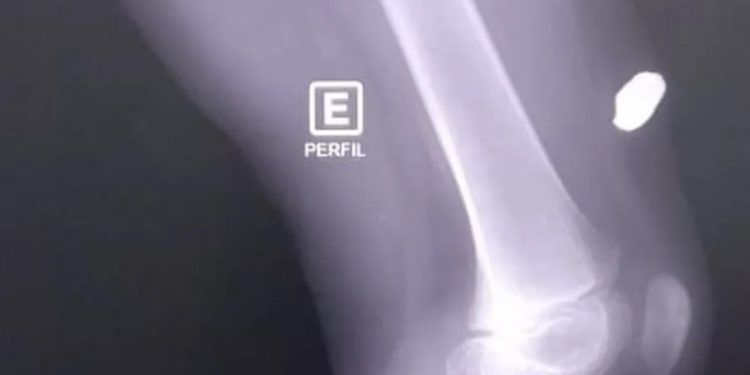

O caso ocorrei por volta das 7h. A bala ficou alojada na perna da criança, que vai passar por cirurgia. “Eu acordei com aquele estalo, eu pensei que tinha quebrado alguma coisa. Ele começou a gritar, desesperado, dizendo ‘Estourou alguma coisa aqui na cama, porque está sangrando a pena dele’. Quando eu fui olhar, a bala estava lá. Fomos olhar quem estava na rua, vimos a viatura. Na hora, eu saí gritando aqui, acho que eles não ouviram. Acho que eles não ouviram e saíram na viatura”, contou a mãe, que não quer ser identificada.